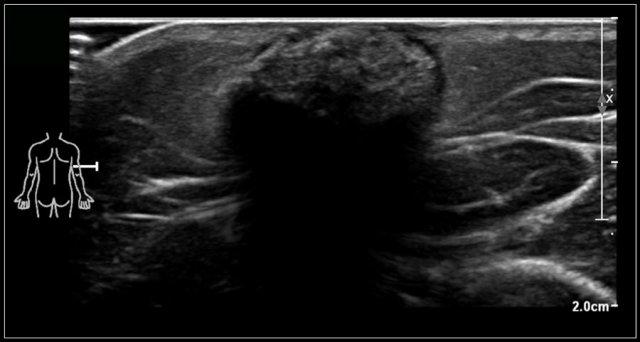

Trên siêu âm thấy hình ảnh phì đại cơ ức đòn chũm.

Có thể ảnh hưởng toàn bộ cơ hoặc một phần cơ.

Đầu ức luôn bị ảnh hưởng, và thường gặp cả đầu đòn.

Có thể giảm âm, đồng âm hoặc tăng âm.

Hình ảnh theo mặt cắt dọc của khối phồng sẽ xác định nguồn gốc từ cơ.

Here a video of a two-month-old boy with a torticollis.

Một khối u được nhìn thấy bên trong cơ ức đòn chũm bị phì đại.

Chẩn đoán là xơ cơ ức đòn chũm ở trẻ sơ sinh